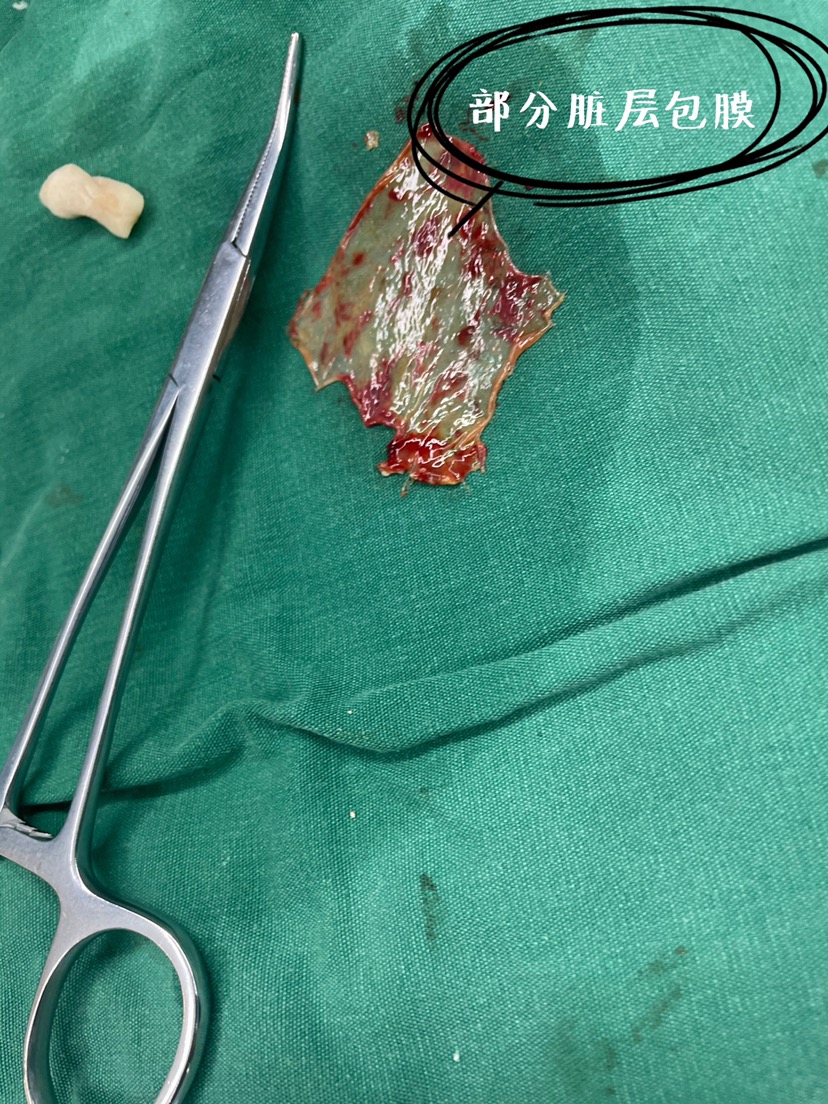

术中所见如下:

硬膜下血肿,打开硬脑膜,见明显的包膜。

清除大量“果冻”样血凝块,同时剔除包膜